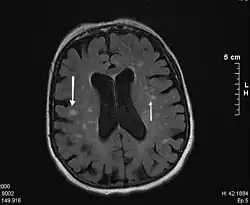

Die Diagnose wird mit einer MRT (Magnetresonanztomographie = Kernspintomographie) gesichert. Diese zeigt in den T2-gewichteten Bildern typische weißliche konfluierende Herde um die Ventrikel und besonders an den vorderen und hinteren Enden der Seitenventrikel eine kappenartige Sklerosezone.